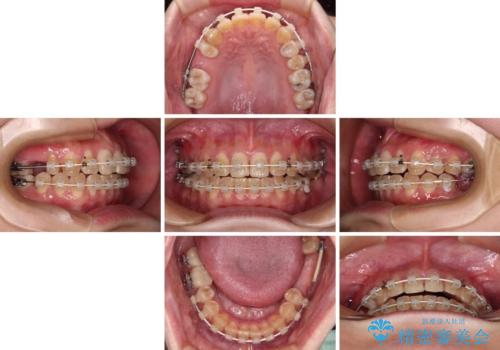

まずはむし歯の治療を行い、その後ワイヤー矯正にて咬み合わせを改善し、途中インプラント埋入を行い、矯正治療後に補綴治療を行うこととしました。